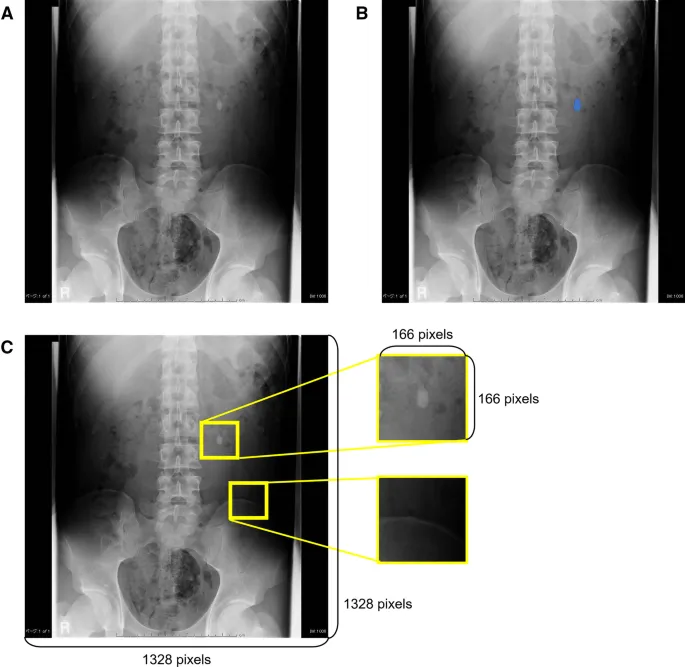

Stone Cold Evidence - Calcifications & Co.

- Renal Calcifications:

- Nephrocalcinosis (medullary/cortical).

- Renal calculi:

- Radio-opaque: Calcium oxalate/phosphate (most common).

- Radiolucent: Uric acid, xanthine.

⭐ Staghorn calculi are typically composed of struvite (magnesium ammonium phosphate) and are associated with recurrent UTIs by urease-producing bacteria.

- Phleboliths: Common pelvic calcifications, often with lucent centers.